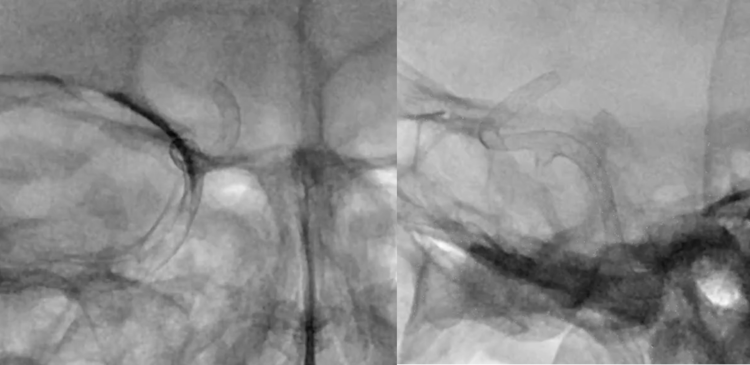

Surpass Streamline释放完毕后,未进行按摩和后处理,显示支架打开的完美状态。

双容积重建结果,显示支架和血管壁贴合非常好